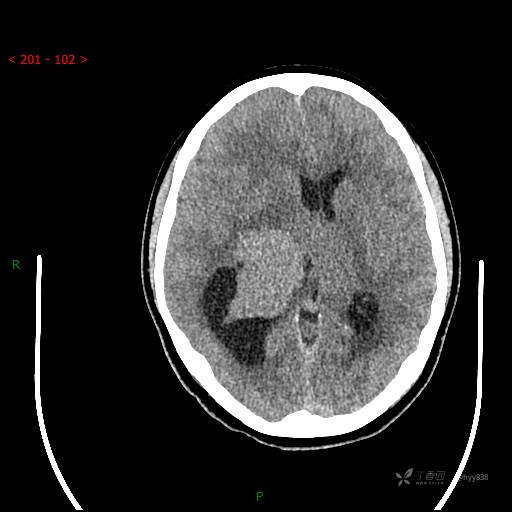

简要病史:患者于1月前无明显诱因出现视物模糊,无明显头痛头晕,无恶心呕吐,无昏迷,无肢体偏瘫等症状,就诊于当地医院头部CT考虑:右侧丘脑、脑室占位。予以对症处置后家属为求进一步诊治来我科,以“颅内占位”收入院。 起病以来,精神、饮食、睡眠欠佳,大小便正常,体力下降,体重无明显变化。

临床诊断:脑室占位

颅脑CT平扫